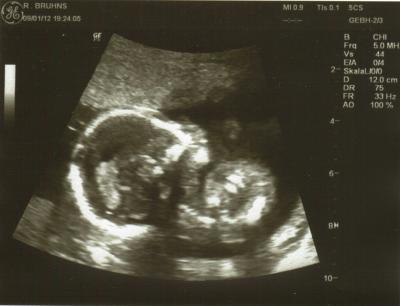

Ich hatte heute nach 6 langen Wochen wieder VU. Das Zwergle entwickelt sich total super, hat bei einigen Daten am US sogar teilweise bereits die 20.SSW ausgerechnet. Gewicht liegt in etwa bei 263 g, Größe zirka 18,2 cm. Kopfumfang ist auch bereits bei 14 cm, wird denke ich wieder ein großer Kopf werden (mein Sohn hatte KU 36). GMH ist total super bei 5,3 cm Länge, also alles in allem prima Werte. Als der Arzt fragte ob wir wissen wollen was es wird war ich ganz still und hab dann nur meinen Freund angesehn. Er dann nach ein paar Sekunden: 'Nein!' Also bleibt es weiterhin bei einer Überraschung Auch meine Blutwerte sind vollkommen in Ordnung. Hab dann heute auch die Zuweisungen fürs Organscreening und für einen Glukosetest bekommen. Wegen meinem Kreislauf solle ich nur zusehen dass ich mehr esse und trinke, was mir aber leider ein wenig schwer fällt. Bin heute bei 17+5 und nächster Termin beim FA ist erst wieder am 5.3. (7 Wochen warten)

Bild zu Auch zurück vom FA - Forum für Juni - Mamis

Toll! Freut mich für dich dass alles so klasse ist. Soolche süßen Bilder, wahnsinn..dieser Arm und diese Hand.. Tolle Qualität! Und großen Respekt an dich..ich könnte das nie, es mir dann nicht sagen lassen..